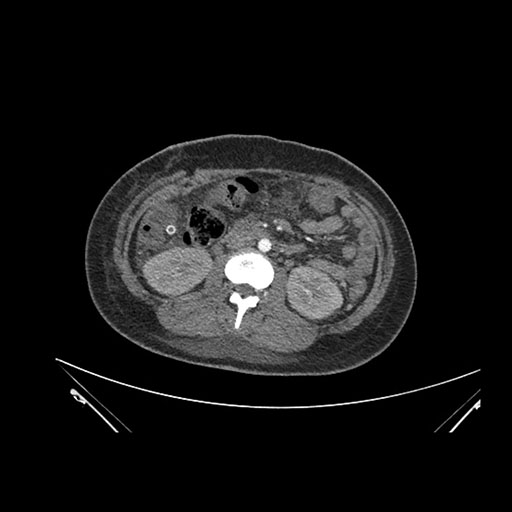

Imaging Analysis

Look through the patient's CT scan to identify any areas of concern for the necessary procedure.

Axial Arterial

Based on initial findings, which issue(s) would you be most concerned about?